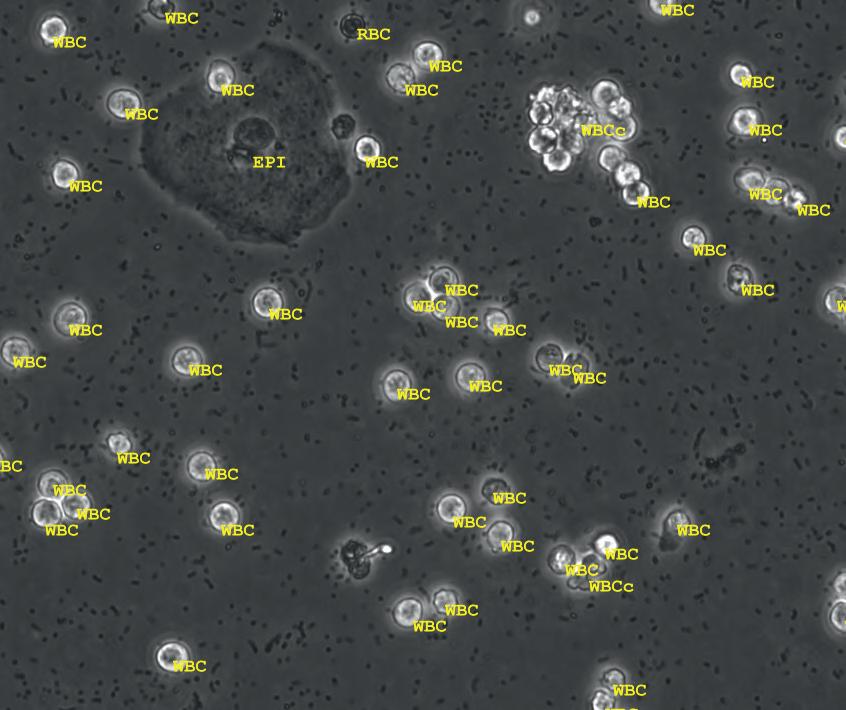

Image: The CytoTracker Leukometer is a portable device that quickly delivers readings based on a single drop of blood (Photo courtesy of RizLab Health)

Handheld White Blood Cell Tracker to Enable Rapid Testing for Infections

Researchers at Rutgers startup RizLab Health Inc. (Princeton, NJ, USA; www. rizlabhealth.com ) have developed an innovative device can rapidly count a person’s white blood cells (WBC), or leukocytes, with a single drop of blood, enabling rapid testing and improved triaging for infections. Called the CytoTracker Leukometer, the device has undergone comprehensive testing, comparing its performance with conventional lab benchtop hematology analyzers used for standard blood tests. These trials confirmed that the CytoTracker Leukometer is at least 97% accurate, thereby meeting established clinical standards. In emergency room settings, the device could expedite the detection of sepsis in patients more swiftly than current methods, which typically involve blood draws and lab testing.